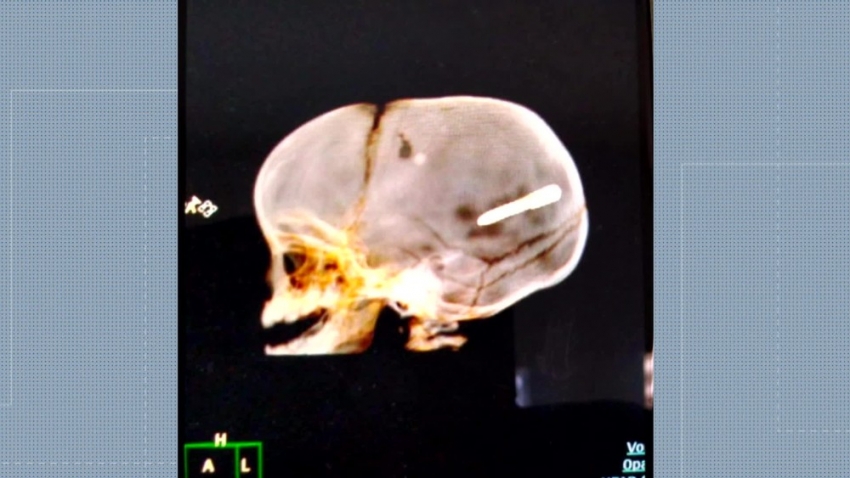

Um bebê de 10 meses está internado em estado grave no Hospital Pedro II, Zona Oeste do Rio, com um prego na cabeça.

O menino, identificado como Wallace Martim dos Santos, teve a cabeça perfurada pelo objeto na noite desta terça-feira (30).

Uma radiografia mostra que o objeto está alojado no crânio do bebê. A família contou para a polícia que o menino estava no colo da mãe, dentro do carro, quando eles ouviram um forte estampido e viram que o neném tinha sido atingido pelo prego. O objeto, segundo os pais do bebê, parecia um dardo onde é colocado gesso em obras.